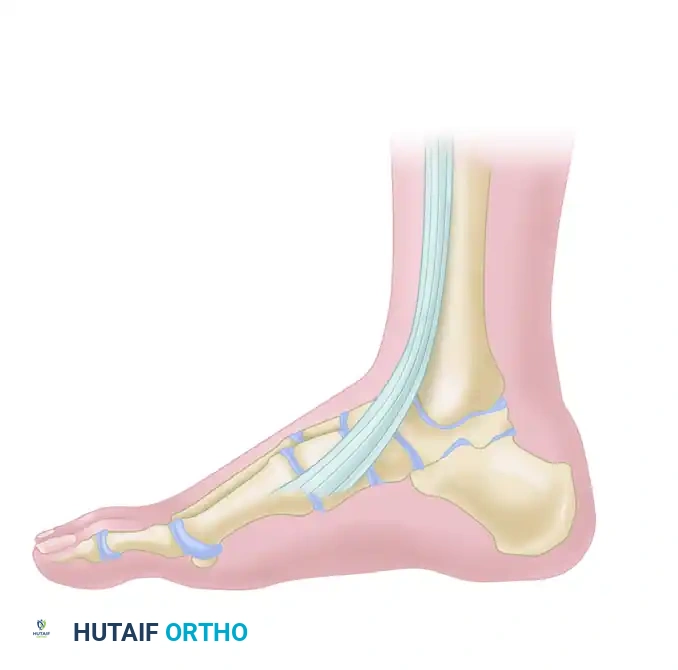

The anterior tibial tendon is the primary dorsiflexor of the ankle joint, responsible for approximately 80% of dorsiflexion power. It plays a critical biomechanical role during the gait cycle: it contracts eccentrically at heel strike to decelerate plantarflexion and prevent "foot slap," and it contracts concentrically during the swing phase to ensure adequate ground clearance of the forefoot. Loss of ATT continuity profoundly disrupts normal gait mechanics.

A profound understanding of the anterior compartment anatomy is requisite for diagnosing and surgically managing ATT disorders. The tibialis anterior muscle originates from the lateral condyle of the tibia, the proximal two-thirds of the lateral tibial shaft, and the interosseous membrane. As it transitions into a tendinous structure in the distal third of the leg, it passes beneath the superior and inferior extensor retinacula.

ASSOCIATED MEDIAL COLUMN PATHOLOGY: THE ACCESSORY NAVICULAR

When evaluating tendinopathies of the medial midfoot, the surgeon must also consider the posterior tibial tendon (PTT) and its relationship with the navicular. While the ATT inserts on the medial cuneiform and first metatarsal, the adjacent PTT inserts heavily onto the navicular tuberosity. The presence of an accessory navicular (os naviculare) is a frequent source of medial column pain, tenosynovitis, and tendinosis that can clinically mimic or coexist with anterior compartment disorders.

An accessory navicular is a secondary center of ossification that fails to unite with the primary navicular bone. It is present in approximately 10-14% of the population. When symptomatic, the PTT, which often inserts anomalously into this accessory ossicle, exerts a continuous shear force across the synchondrosis during the stance phase of gait. This leads to microfracture, inflammation, and progressive loss of the medial longitudinal arch.

The posterior tibial tendon is then advanced and sutured directly to the periosteum and the raw cancellous bone of the navicular to restore its mechanical advantage in supporting the medial longitudinal arch. The wound is closed in layers, and the patient is placed in a non-weight-bearing cast in slight inversion and plantarflexion for 4 to 6 weeks to protect the tendon repair.